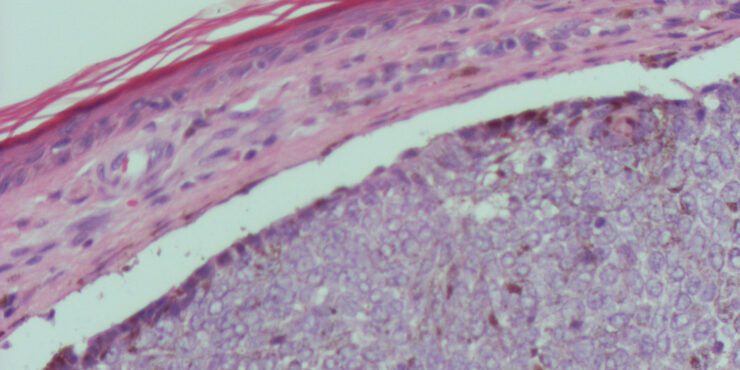

Pernio = الشرث Pernio (Chilblain) Pernio (chilblain) is a distinct form of cold-induced injury in which humidity, in addition to cold, plays a role in inducing the condition . There are acute and chronic presentations. Chilblains classically presents in young to middle-aged women as painful, burning, and/or pruritic erythematous to violaceous or cyanotic macules, papules, […]